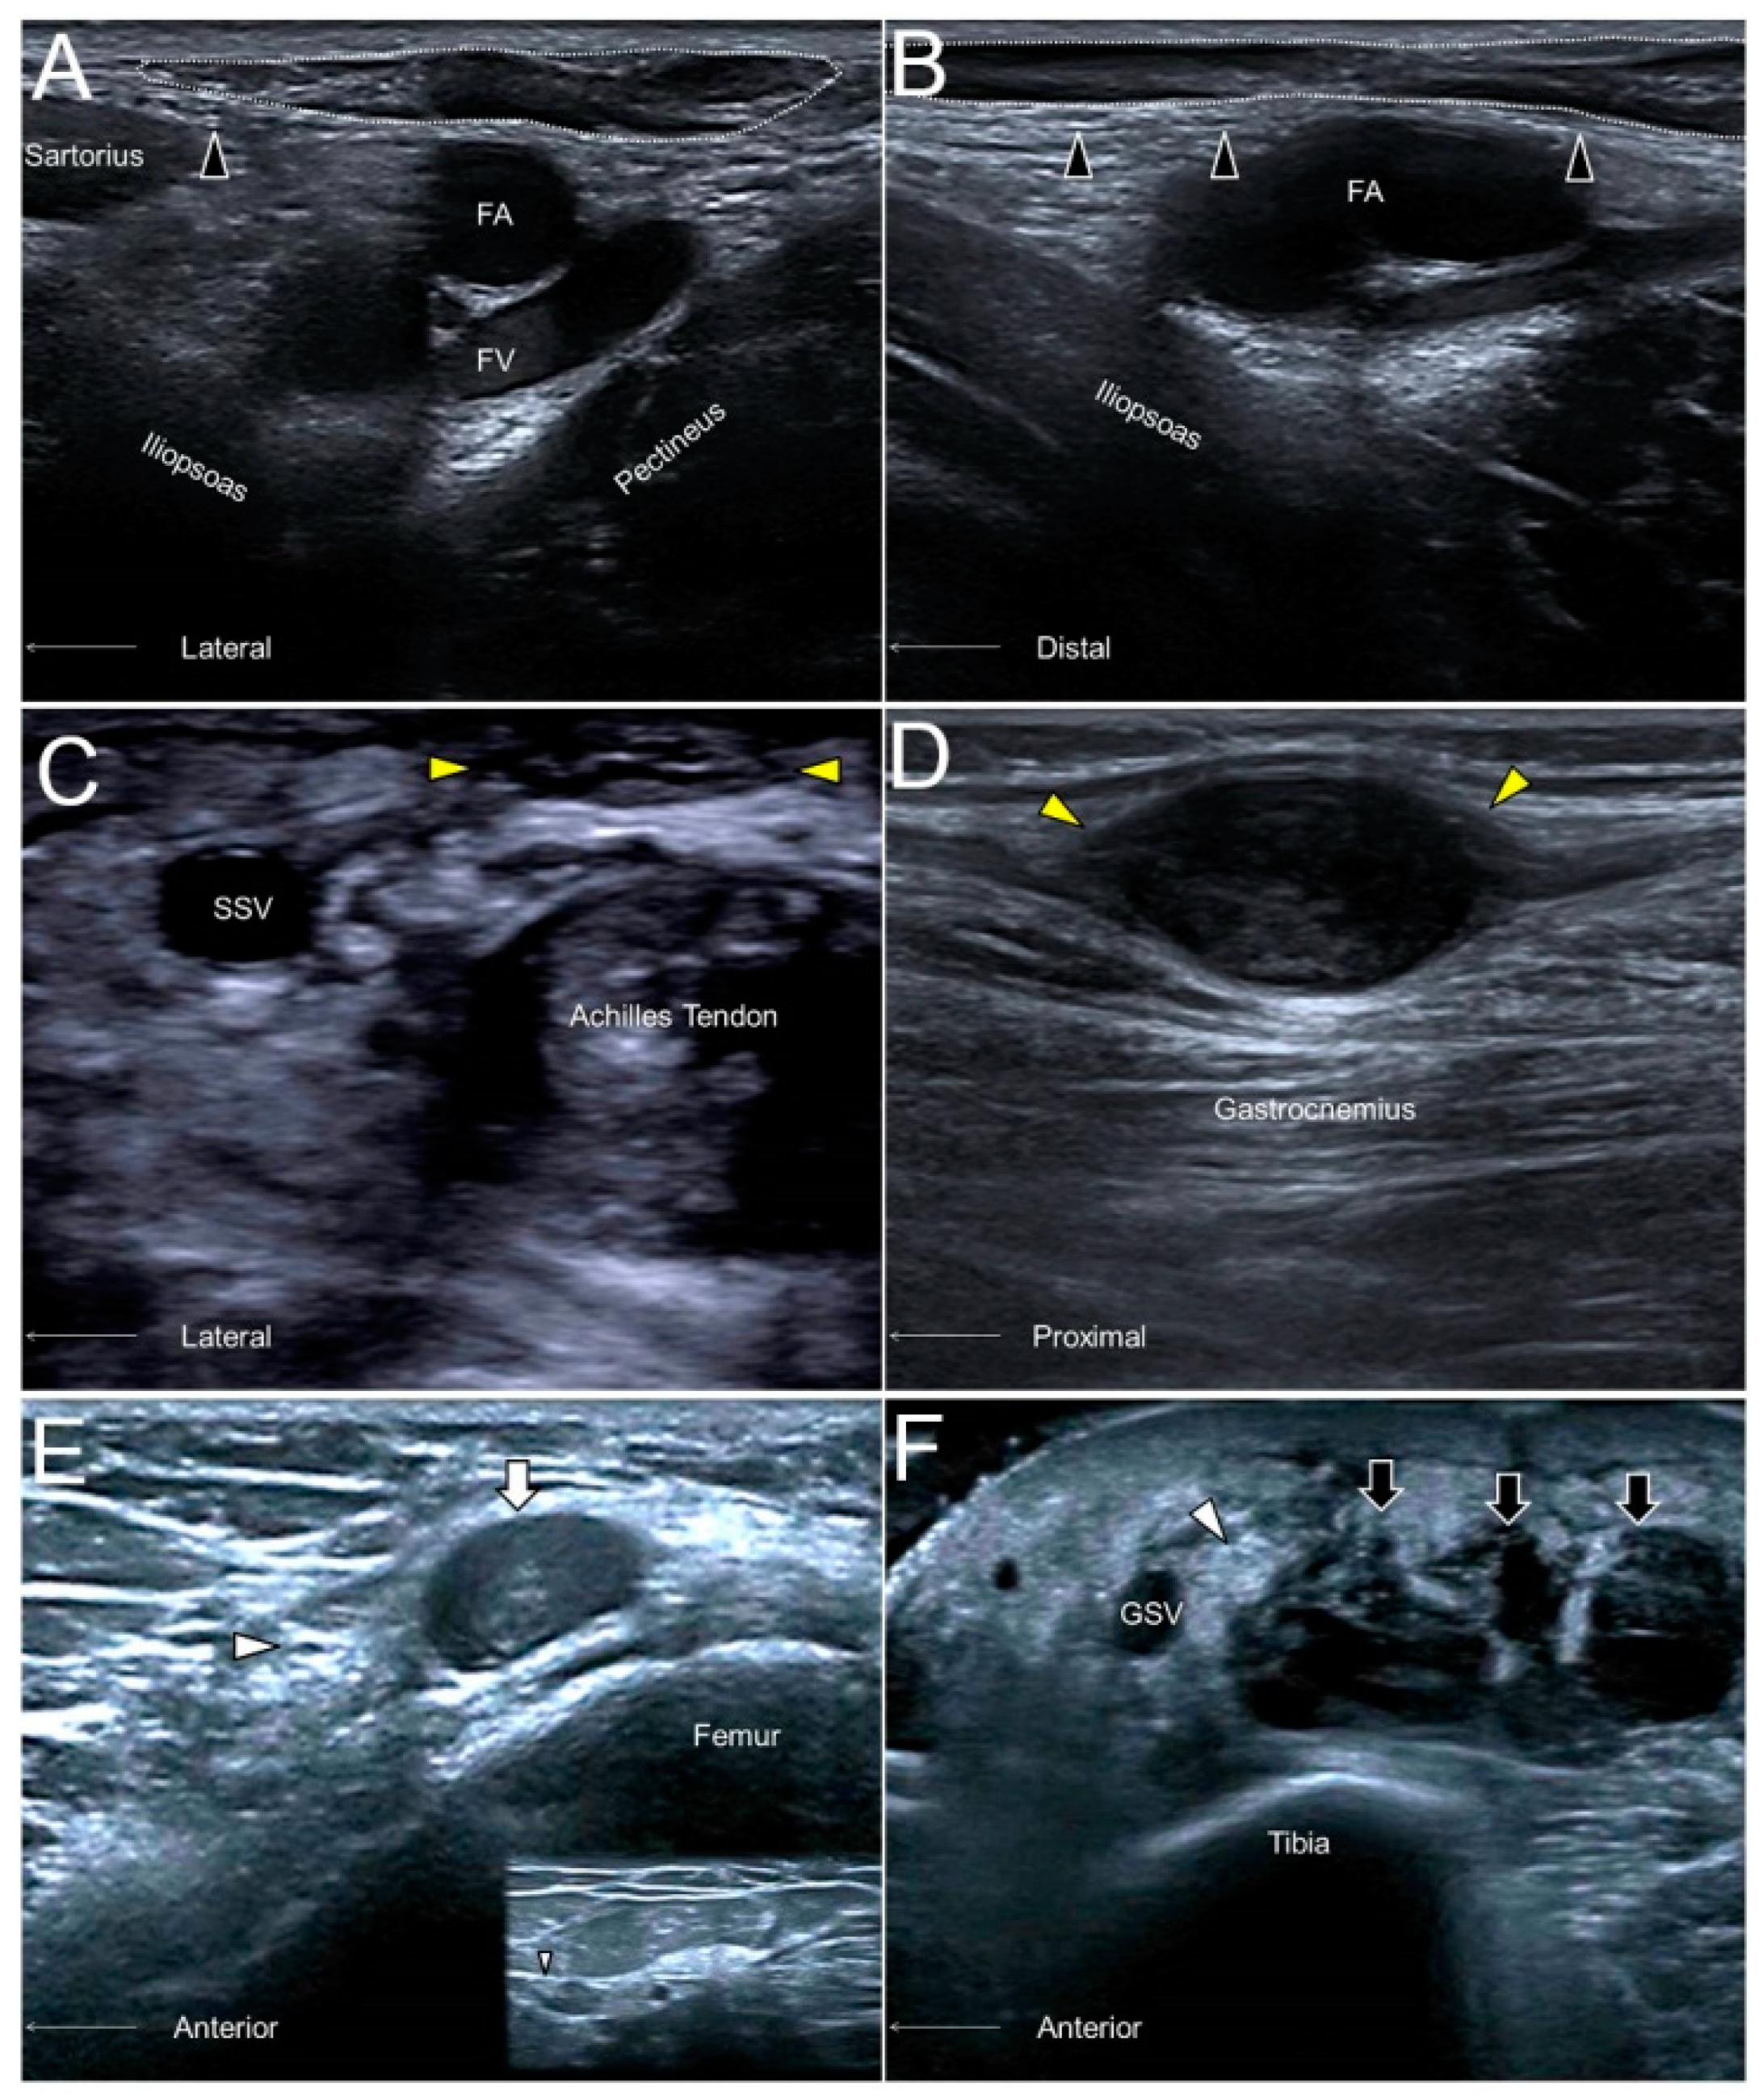

Figure 10. The short- (A) and long- (B) axes imaging of the anterior femoral cutaneous nerve (black arrowhead) compressed by an inguinal lymph node (dotted circle). A sural nerve (yellow arrowhead) neuroma in a male following Achilles tendon repair (C). A sural nerve schwannoma in a female with chronic calf pain (D). A swollen segment (white arrowhead) and a relatively normal portion (smaller white arrowhead) of the saphenous nerve adjacent to a hematoma (white arrow) of the distal femur (E). A thickened saphenous nerve (white arrowhead) next to serosanguinous fluid (black arrow) in a female with a degloving injury of the leg (F). FA, femoral artery; FV, femoral vein; SSV, small saphenous vein; great saphenous vein.

10.3. Clinical Implication

Like in most of the cutaneous nerves, an AFCN neuropathy commonly ensues due to iatrogenic injuries, e.g., a total knee replacement. Other causes comprise vein stripping, bypass grafting, lipoma excision, lymph node compression (Figure 10A,B), and abscess removal. US imaging may reveal segmental nerve swelling or, more severely, neuromas in symptomatic cases [28].

13.3. Clinical Implication

The sural nerve is in proximity to the small saphenous vein and can be injured during surgeries for varicose veins. Another cause of nerve injury would be related to Achilles tendon ruptures, whereby the nerve may be entrapped by an adjacent hematoma (Figure 10C). The nerve can also be traumatized by a foreign body due to its superficial lateral position at the distal segment. Neuromas are not rare sonographic findings in patients with suspicion of sural nerve neuropathies (Figure 10D) [34].

14.3. Clinical Implication

The saphenous nerve, especially its infrapatellar branch, is vulnerable to injury during surgical interventions of the anterior medial knee. Common procedures that elicit a saphenous nerve injury include medial arthrotomy, meniscectomy, arthroscopic anterior cruciate ligament repair, and total knee replacement. Contusion to the lower extremity is another frequent cause of saphenous nerve injury (Figure 10E). In patients with a degloving-type injury, US imaging may reveal a swollen nerve segment floating inside the anechoic fluid collection between the skin and the superficial fascia (Figure 10F) [36].